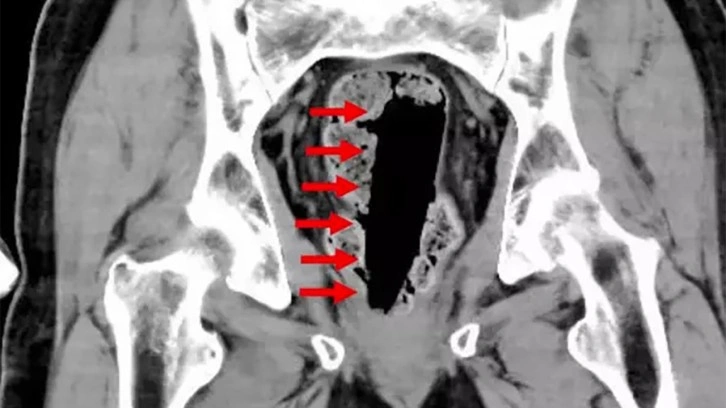

Bilgisayarlı tomografi taraması, parkinson hastası olan isimsiz adamın anüsünün içinde 35x35x120 mm ölçülerinde yapıştırıcı kabının bulunduğunu gösterdi. Şişe, ipin çekilmesiyle başarıyla çıkarıldı ve adam ertesi gün taburcu edildi.